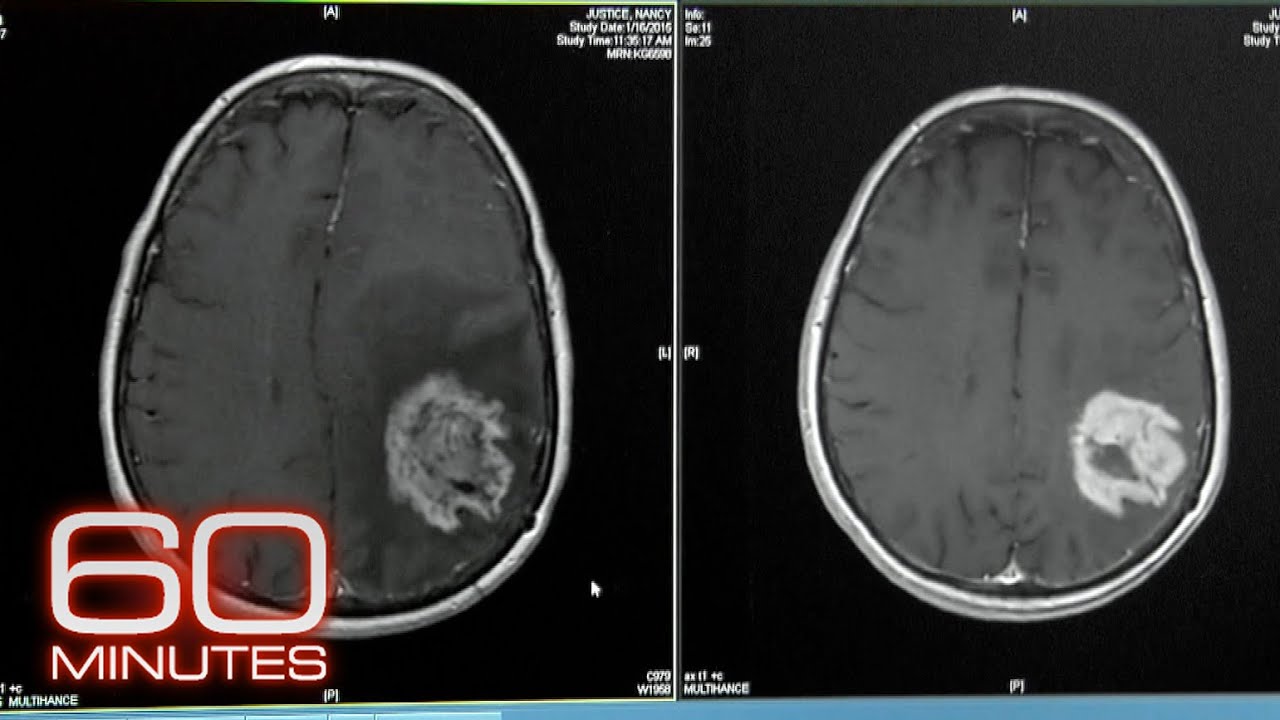

o tártaro câncer usando o nosso próprio sistema de defesa Este é o princípio da imunoterapia ao contrário dos tratamentos convencionais como Radio e quimioterapia não se ataca diretamente o tomou a imunoterapia estimula a resposta imunológica do paciente as células tumorais neutralizam as defesas do sistema imunológico permitindo que as células cancerosas se multiplicarem pelo corpo Existem várias formas de acordar em ensinar o sistema imunológico a eliminar as células cancerosas e e a imunoterapia utiliza várias ferramentas da vacinas terapias entre proteínas do sistema imunológico e são capazes de reconhecer e eliminar as células indesejadas E imunomoduladores esses

são medicamentos que estimulam o sistema imunológico outra estratégia é a terapia celular quando um tipo de glóbulo branco chamado linfócito é colhido do paciente e modificados geneticamente para reconhecer células cancerosas este super linfócito é injetado novamente no organismo para atacar o câncer usadas atualmente para tratar o câncer no sangue e melanoma em estágio avançado estas terapias fizeram crescer a esperança de se tratar outros tipos de câncer mas a imunoterapia só funciona na minoria dos pacientes seus efeitos colaterais podem ser importantes como uma reação autoimune do organismo as células saudáveis um outro problema é o custo